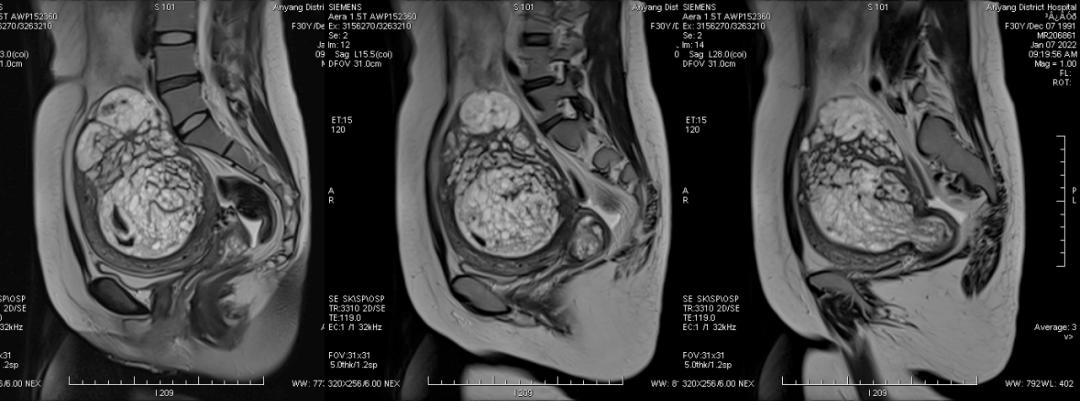

病例一

女,18 岁,孕 19 周 6 天,妊娠合并胎盘部分性葡萄胎 1 月余,病灶与子宫肌层分界清晰。

孕早 期因胃痛曾应用氨苄西林粉、西咪替丁、维生素 B6、山莨菪碱、胃炎颗粒、胃灵颗粒、吗丁啉对症治 疗。 外院彩超提示: 宫内妊娠,单活胎,胎儿室间隔缺损,胎盘 下方见异常不均质回声,范围约 109*41*108 mm,内呈蜂窝状改变,与胎盘分界不清,考虑部分性葡萄胎可能,建议终止妊娠。 为进一步终止妊娠就诊我院。